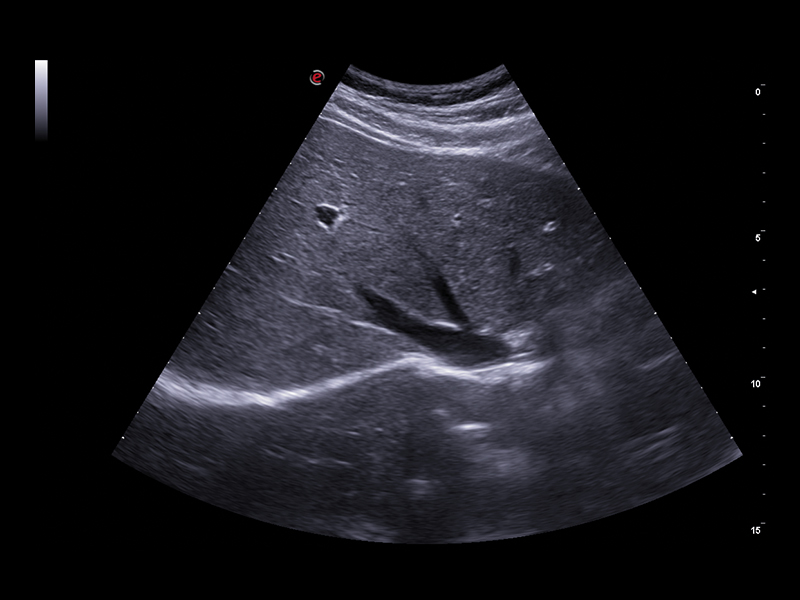

Clinical Images

Liver care clinical image